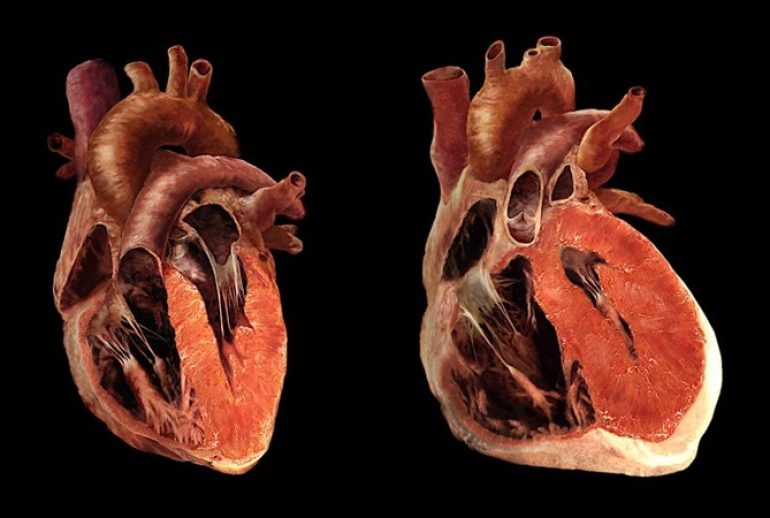

بزرگ شدن قلب یا کاردیومگالی یک وضعیت پزشکی است که در آن قلب به دلایل مختلف بزرگتر از حد طبیعی میشود. این وضعیت میتواند نشانهای از یک مشکل زمینهای جدی باشد و نیاز به توجه پزشکی دارد. در این مقاله، به بررسی دقیق علل، علائم، روشهای تشخیص و درمان کاردیومگالی میپردازیم.

کاردیومگالی معمولاً نتیجه یک بیماری یا شرایط دیگر است که باعث افزایش فشار بر قلب میشود. برخی از علل شایع عبارتند از:

- فشار خون بالا: این شایعترین علت بزرگ شدن قلب است. فشار خون بالا باعث میشود قلب سختتر کار کند و در نتیجه عضله قلب ضخیمتر میشود.

- بیماریهای دریچه قلب: اختلال در عملکرد دریچههای قلب میتواند باعث افزایش حجم کار قلب شود.

- بیماری عروق کرونر: تنگی رگهای خونرسان به قلب میتواند منجر به ضعف عضله قلب و در نتیجه بزرگ شدن آن شود.

علاوه بر این، عواملی مانند کمخونی، مشکلات تیروئید، بیماریهای ریوی و حتی ورزشهای سنگین و طولانی مدت نیز میتوانند باعث بزرگ شدن قلب شوند.